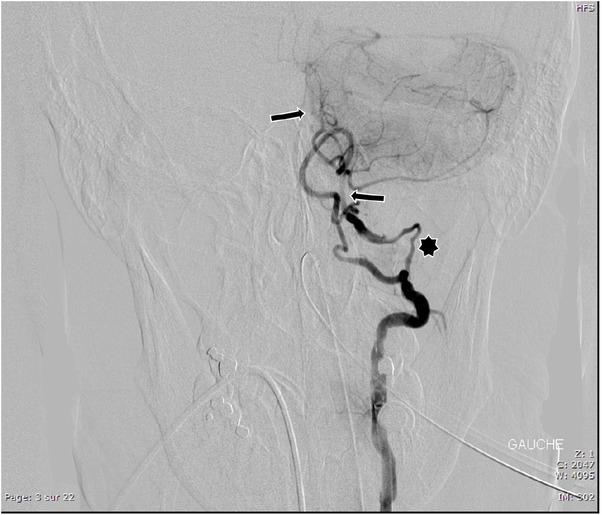

Fig. 2